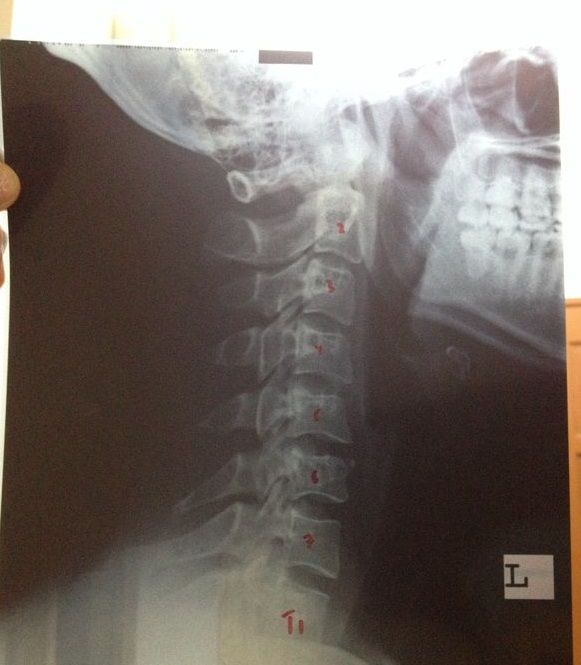

颈椎强直失去曲度

有经验的大大或医生帮帮忙看一下这张X光片,这颈椎是不是强直和失去曲度 ?谢谢

只有在颈部出现吗?

有没有什么不舒服的症状?

搜寻一下 僵直性脊椎炎(Ankylosing Spondylitis,AS)

看是否跟你的状况很像

如果只是单单出现在颈部,没有钙化等问题

应该是肌肉张力问题或是不良姿势导致

颈部,头部,身体,都是左侧一直有酸酸重重的感觉,头部左侧也会昏但不是天旋地转那一类。。。

颈椎有问题导致手有问题我可以明白,可是不明白难道脚也会受影响 ?

MRI也照了,椎间盘基本上是没问题。。。 本帖最后由 Johnny仔 于 21-3-2014 10:53 AM 编辑